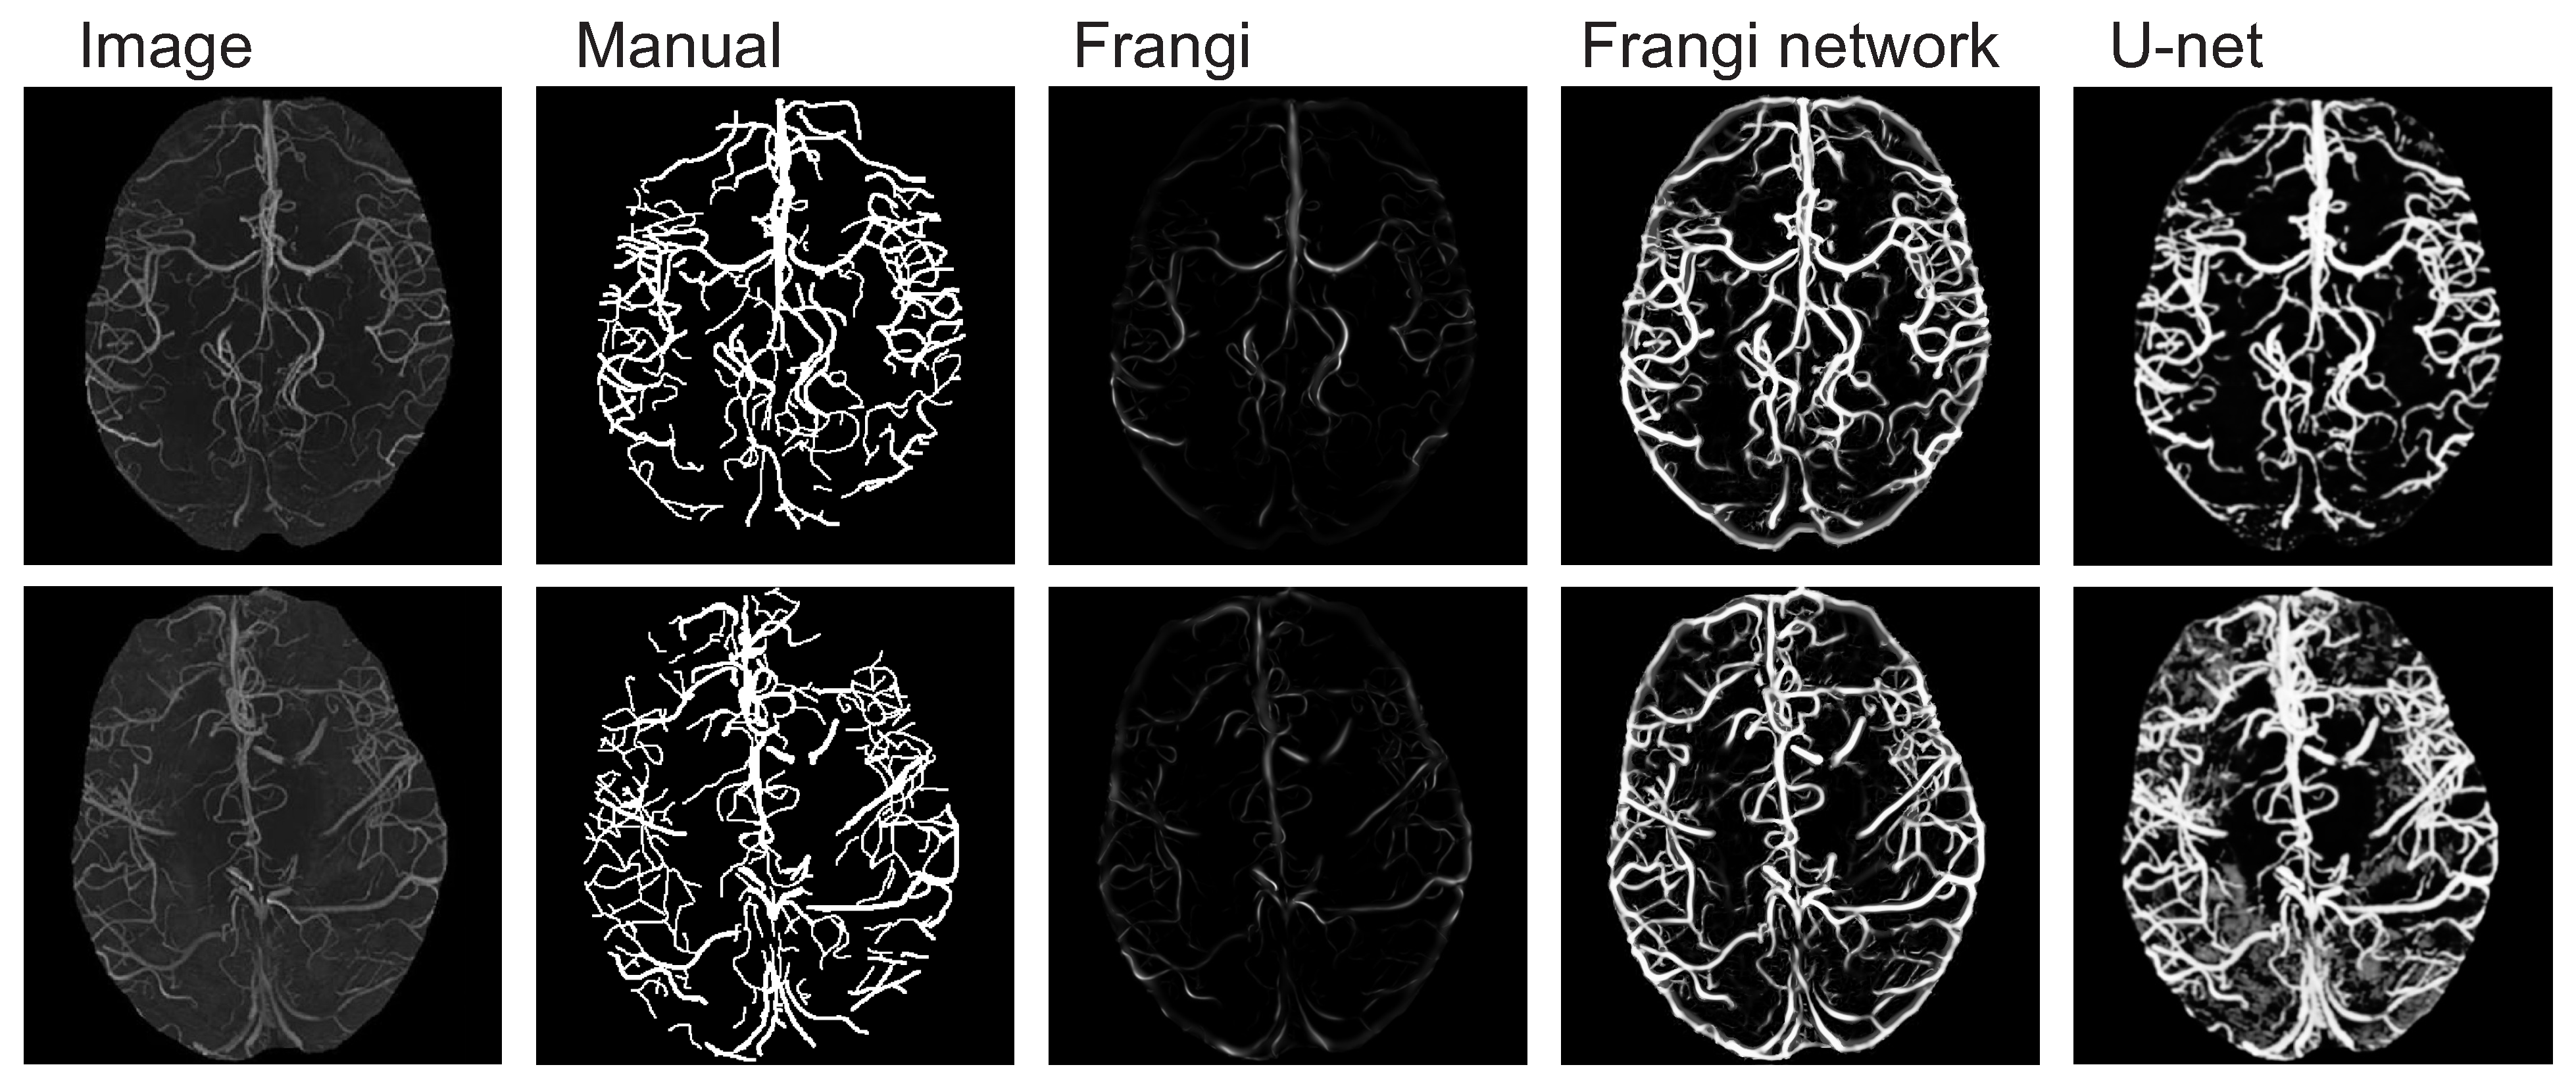

The results of the segmentation performance of each method can be seen in Figure 3, Figure 4 and Figure 5 and in Table 1, Table 2, Table 3 and Table 4. Values in the tables are averaged. The last row of Table 1 contains the average execution time of the algorithm on the retina set given in seconds. We calculated Sensitivity, Specificity, Intersection of Union (IoU/Jaccard), Volumetric Overlap Error (VOE) [44] and F1-score/Dice to make the results more comprehensive. We found those metrics most appropriate. Other popular scorings like Average Symmetric Surface Distance (ASSD) that measures the average of all distances for every point from one object to the other and vice versa are not suitable for tubular structure segmentation but rather for regions or volumes segmentation [45,46].

Figure 4.

Segmentation results on the brain MRI dataset.

Both the results obtained in Table 1, Table 2, Table 3 and Table 4 and the visualizations in Figure 3, Figure 4 and Figure 5 prove that the Frangi neuron fulfills its role as a detector of second-order structures. Both AUC ROC and other evaluated metrics consistently show that the proposed network based on Frangi neurons performs better, and, in borderline cases, generally no worse than the stationary Frangi filter. On the other hand, the qualitative advantage of the obtained segmentations over the U-net architecture is strongly evident. This is not due to the weakness of this universal and efficient architecture like U-net, which is a kind of state-of-the-art solution for segmentation tasks. It is simply due to the fact that model parameter fitting is performed on the basis of a one-element learning set. It can be said that the proposed network based on Frangi neurons can be classified among one-shot segmentation approaches. This reveals the great flexibility of the proposed architecture and may be its advantage over universal models such as U-net in some specific applications. The results on the retina set are much worse than, for example, in [47], because the U-net was trained on only one image (one-shot learning) and not on the full 20-element training set. The limitation on the size of the training set was intended to show the limitations of the models purely based on convolutional filters (U-net-like architectures). The Frangi filter performances on all datasets in not poor as it might be expected. As can be seen in Table 2 and Table 3, specificity, IoU and F1-score factors are quite similar to those of the Frangi network. In the case of the Frangi filter, however, the sensitivity value is lower, which means that the filter without the optimization procedure performs worse in identifying true positive values. On the other hand, the fact is that the Frangi filter on the tested datasets performs better than the U-net if this deep neural network is not trained on a sufficiently large dataset. A single image in the training set is enough for the Frangi network using the Frangi neuron to optimize its weights to detect the relevant image fragments. Compared to the Frangi filter alone, the results returned by the network have much stronger contrast. Frangi filtering has the disadvantage of highlighting the boundaries of an area of solid colour as the location of second-order structures. This is clearly visible in the retina set (see Figure 3). This phenomenon cannot be eliminated in a network architecture using only Frangi neurons because it is a feature of a Hessian-based approach. If the filtered area does not have such clear boundaries, this effect does not occur as can be seen, for example, in the coronary artery dataset (see Figure 5). In Figure 3 and Figure 4, the proposed Frangi neuron model might have bias for segmenting the contour. This is typical behaviour of any method that uses various types of edge detectors. In practice, if an image is known to have a globally definable edge separating the area of interest from the background, it is eliminated from the segmentation process by applying an image mask. Such an edge removal procedure was also used in [40]. Thus, this area does not affect the physician or clinician’s decision, since its removal is a well-known practice. For the datasets we considered, a single image was insufficient for the U-net to produce generalizations of the segmentation process despite the fact that it uses image augmentation analagous to that of the Frangi network. Trained on a single image, the U-net either removes too many parts of the image or leaves fractions of the image that do not contain the desired structures. The ROC AUC of the Frangi network has the largest (best) values of all tested methods for all datasets. The computation execution time on the U-net is about faster than on the Frangi net. The Frangi net performs more than seven times faster than the Frangi filter using the same set. We did not optimize the speed of the Frangi neuron because we used the available standard Tensorflow and Keras functions in its implementation, so we assume that its performance can be improved. In summary, the Frangi neuron met the expectations and is an effective component of the network performing segmentation of various types of second-order structures. In most advanced deep neural one-shot network models for image segmentation, the authors use pretrained models on large and comprehensive image datasets [48,49]. This is an important limitation because the most popular image databases such as imagenet [48] and COCO [50] do not contain medical modalities. In contrast, solutions based on Hessian matrix analysis are immediately ready to detect tubular structures. In medical practice, we often have a very limited number of medical images presenting the modality of interest to physicians, on which a particular biological structure can be seen. In such case, even transfer learning is problematic due to the high complexity of the deep learning model and the shortage of training data. The remedy might be the use of image augmentation, which we also applied in this work for the U-net.